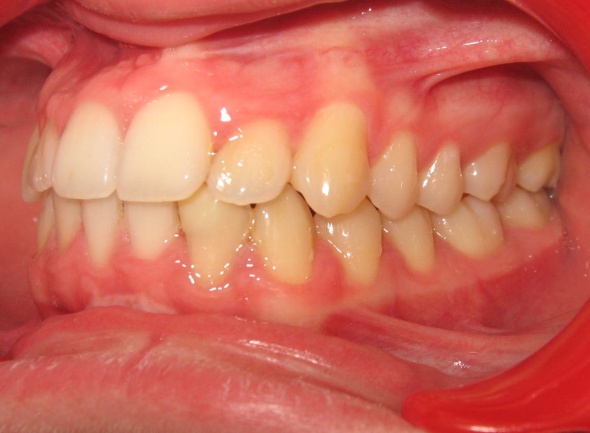

Ce cas illustre parfaitement que l’orthodontie ne peut pas se résumer à un simple alignement des dents. Ici, l’exclusion de la canine supérieure gauche (23) pouvait faire croire à un manque de place dû à un excès de volume dentaire. En réalité, un diagnostic précis a révélé deux causes : une endomaxillie (palais trop étroit) et une avancée anormale de l’hémiarcade gauche, qui empiétait sur l’espace de la canine. Le traitement a consisté à élargir le maxillaire par disjonction, puis à réaligner les dents sans extraction, en restaurant l’harmonie occlusale.

Le traitement a été conservateur, sans extraction, grâce à une thérapeutique de gain d’espace adaptée. L’arcade a retrouvé sa largeur, son équilibre et son esthétique, par la restitution d’une architecture osseuse et dentaire cohérente. L’occlusion est désormais fonctionnelle, stable et conforme aux rapports naturels entre les deux arcades.